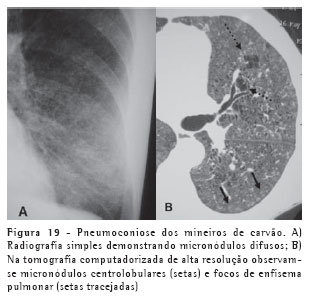

A pneumoconiose dos mineiros de carvão (Figura 19) assemelha-se muito à silicose, sendo praticamente impossível diferenciá-las apenas com os achados de imagem, apesar de os nódulos silicóticos geralmente serem maiores.